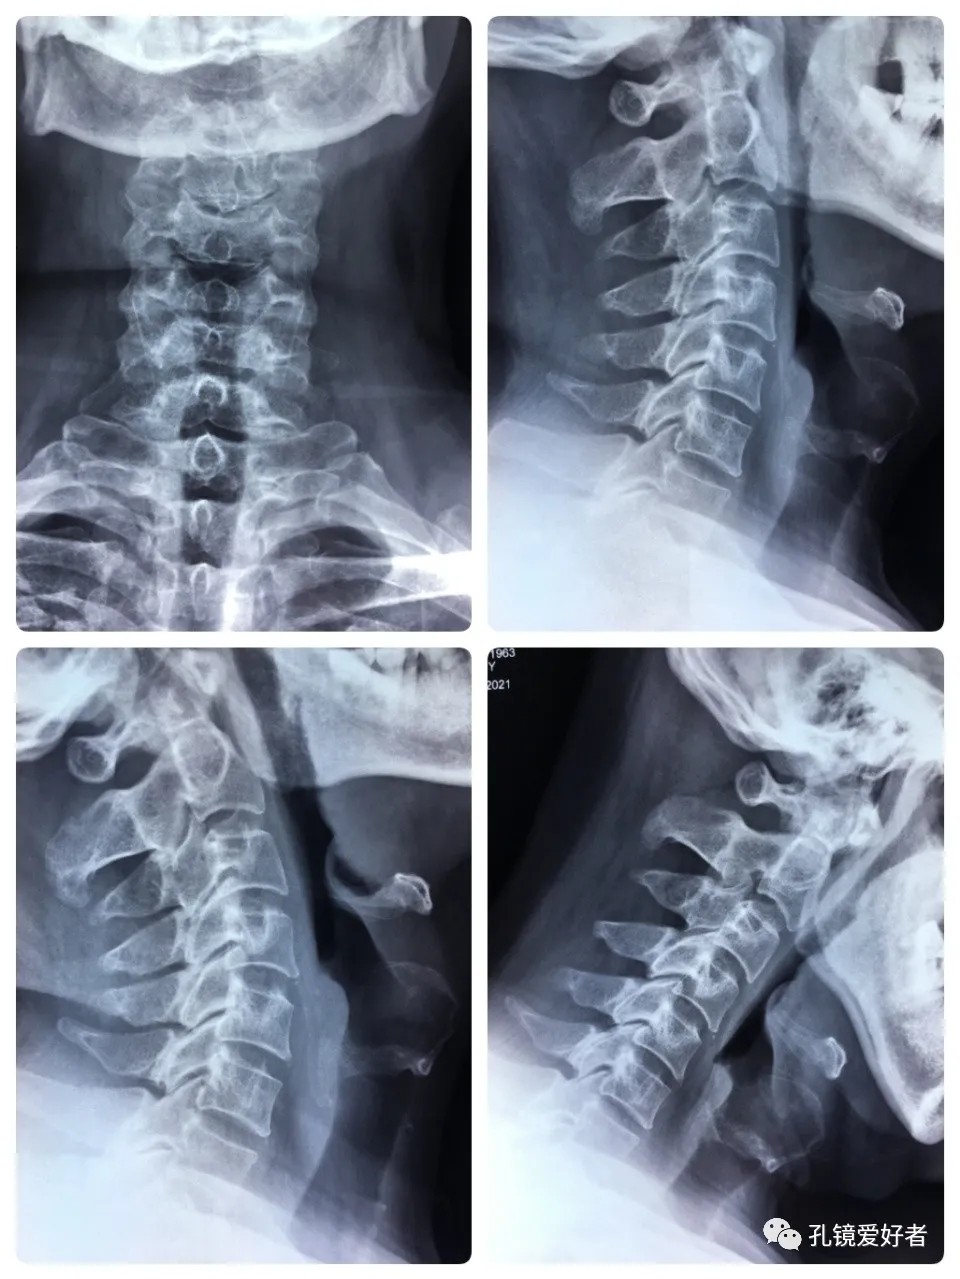

The PA and lateral and flexion-extension position of cervical spine